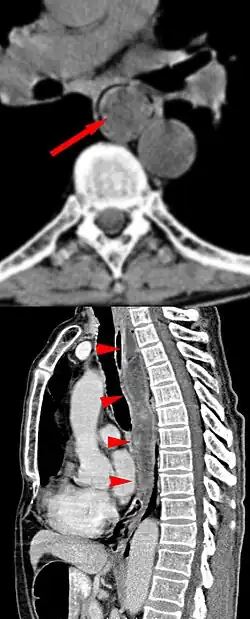

Wenn der Tumor eindeutig Fett enthält, ist dieses in der Computertomographie oder Kernspintomographie nachweisbar und kann so zur Abgrenzung gegen andere Tumoren hilfreich sein.